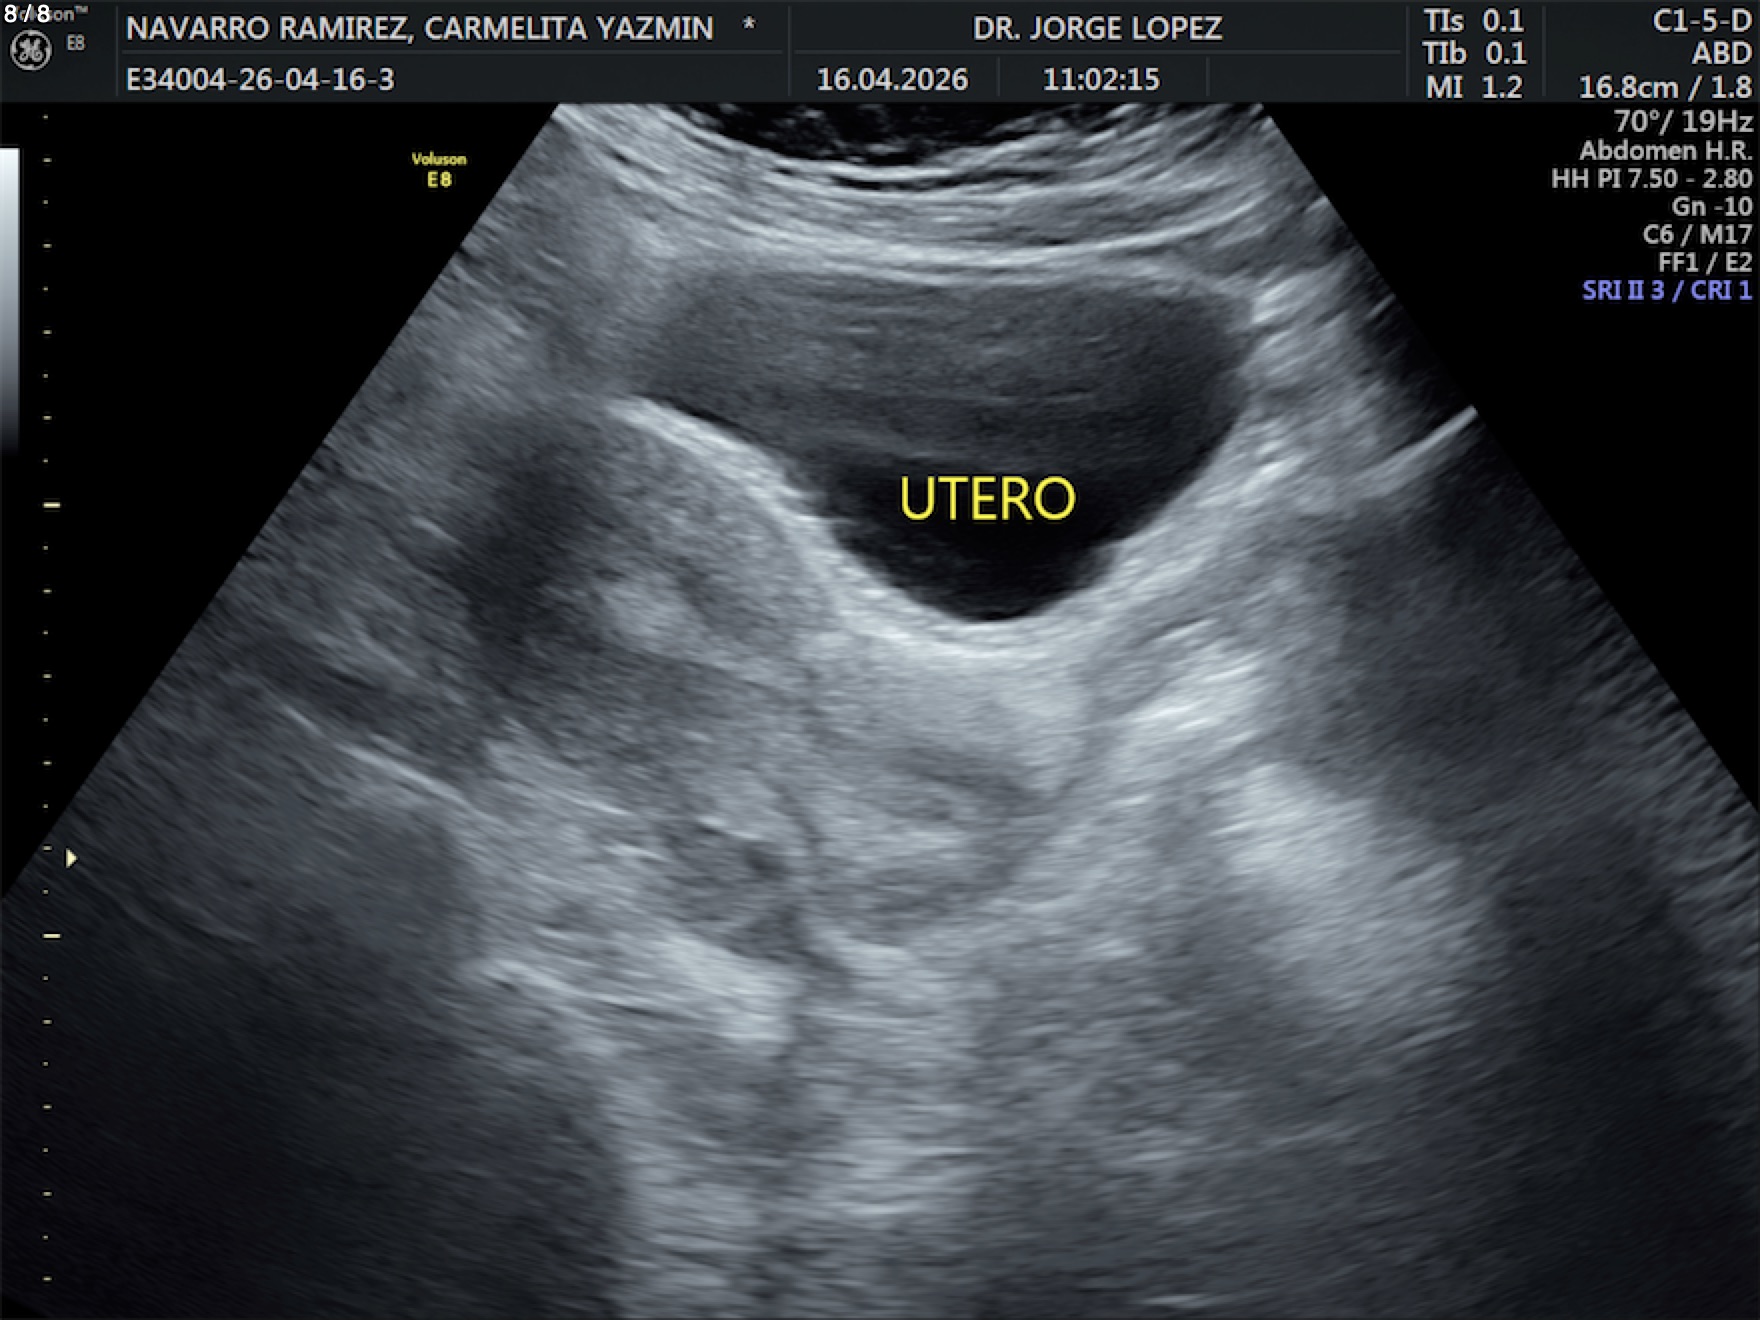

Navarro Ramirez Carmelita Yazmin - Unnamed